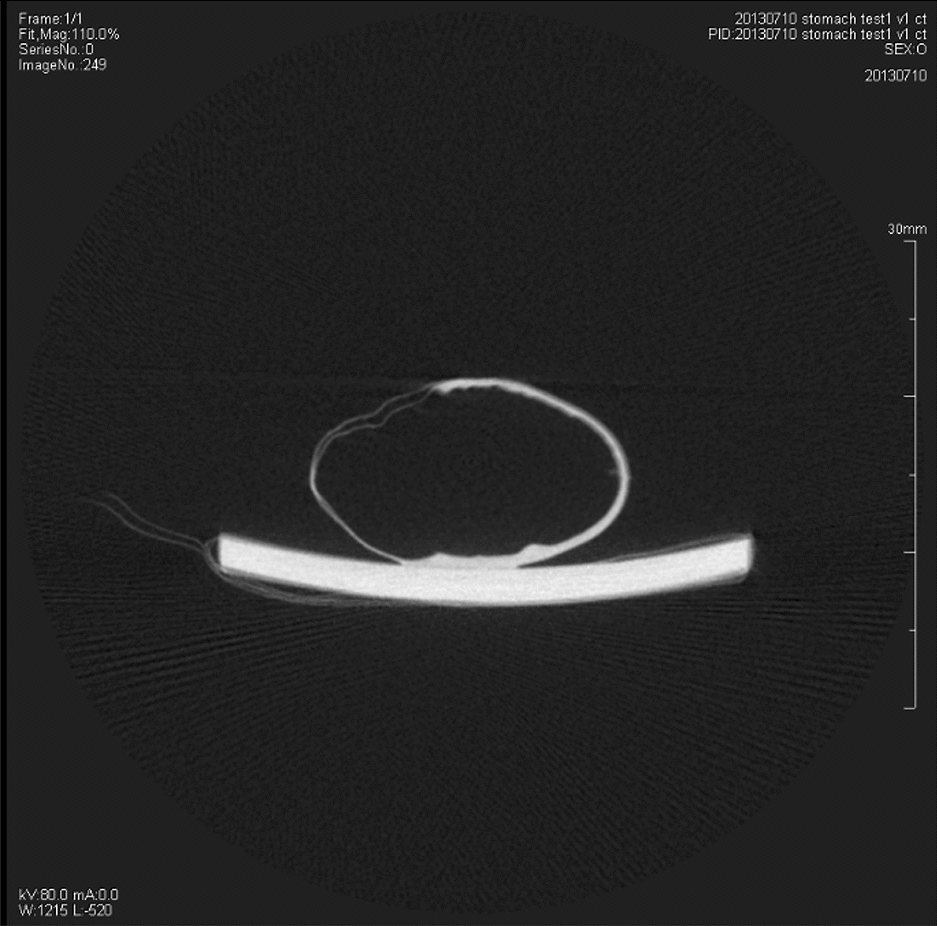

CT images of the same rats’ gastric specimens

The XILPCI 3-dimensional slices were rebuilt by means of a filter back projective algorithm. As shown in Fig. 3, the details can be visualized inside the gastric tissue from under the gross anatomy and the gastric inner surfaces clearly presented longitudinal branching wrinkle and gastric pits.

Fig. 3.

The XILPCI transverse CT images of the rats’ gastric specimens in Fig. 1. a The transverse images along the black line a, g and j are shown in Fig. 1. There are transverse CT images of a 4-week-old rat stomach. It can clearly show that there are grey changes in different gastric structures. The thickness of the gastric fundus and corpus are the same as the XILPCI image shows equal width of gastric wall, and it is obvious that there are multiple bulges in the fundus of the 4-week-old rat stomach. b The transverse images along the black line b, h and k as shown in Fig. 1. The XILPCI images show the wider gastric corpus than the fundus but thicker walls of gastric corpus than that of the fundus. This obviously shows that there are grey changes in the different gastric structures and the duodenum. The bulges have decreased in the fundus of the 6-week-old rat stomach. c The transverse images along the black line c, i and m as shown in Fig. 1. It can obviously be seen that there are many gastric corpus wrinkles in the 12-week-old gastric specimen. ★★★ represents the wrinkles of the gastric fundus. 1 Cardia, 2 Gastric Corpus, 3 Gastric Fundus, 4 Pylorus

Traditional absorption CT images of a normal gastric specimen were obtained by SIEMENS Inveon Scanners with minimum resolution of 11 μm and Inveon Acquisition Workplace with 1.5 Service Pack. The X-ray energy was 80 keV and 400 μA. The absorption CT image of a gastric specimen was Fig. 4. However, it was not clearer than gastric phase-contrast images and the wall fold of the normal gastric specimen cannot be observed.

Fig. 4.

The traditional absorption CT image of the normal rat’s gastric specimen